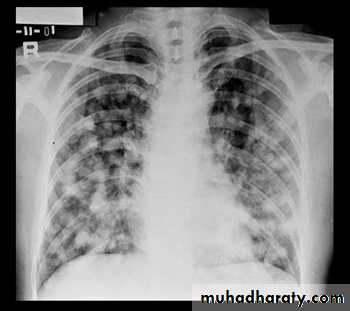

Miliary Tuberculosis. A cone-down view of a frontal radiograph demonstrates innumerable micronodular opacities characteristic of micronodular (miliary)

interstitial disease.

Transbronchial biopsy demonstrated caseating granulomas containing acid-fast bacilli.

Miliary TB

a frontal radiograph demonstrates innumerable micronodular opacities characteristic of micronodular (miliary) interstitial disease. Transbronchial biopsy demonstrated caseating granulomas containing acid-fast bacilli.Tuberculoma